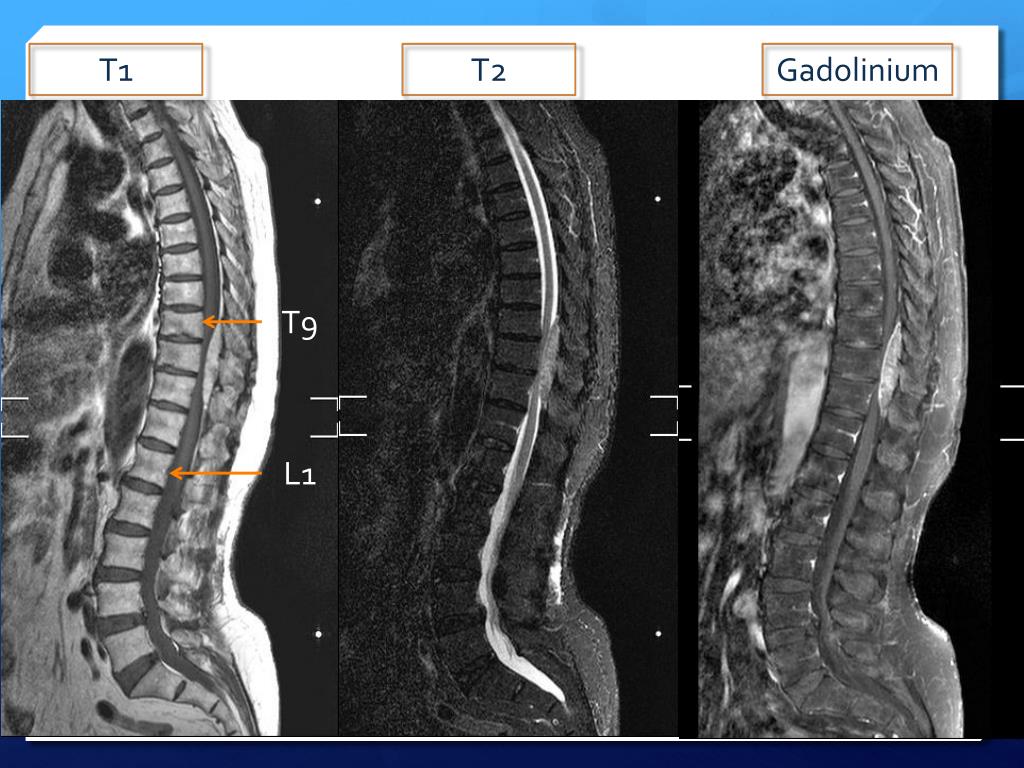

E N D

6. Brief history Left leg pain & numbness x 1 month Dr. Lee OPD MRI: T9 -11 epidural spinal tumor + cord compression L4/5 HIVD Admission for operation

8. Problem List & plan T9-11 epidural spinal tumor Arrange laminectomy and tumor excision

9. 11/08 T9-11 laminectomy and epidural tumor grossly total excision

10. Hospitalization course 11/08 T9-11 laminectomy and epidural tumor grossly total excision Reheab. Left leg numbness and weakness Bedside PT 11/10 Stand up  11/15 Discharge PATHOLOGICAL DIAGNOSIS: Lipovasculartissue, compatible with angiolipoma